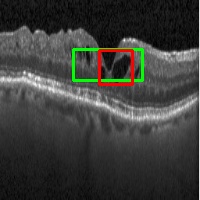

Figure 4: Predicted ROI (in green) for DME detection. Ground Truth is in red.

The ROIs derived with models trained using different ratios (1:R) of images with labels and with labels + localisation annotation are shown for 3 sample test images in Fig.2. The results for Mbsubscript𝑀𝑏M_{b} (last column) are diffuse ROI covering almost the entire image. With the addition of more and more images with localisation information during the training phase, the ROIs improve progressively and we get the best overlap with the FFRs when R reaches 1. The intersection over union (IOU) metric was used to help quantitatively assess the derived ROIs against the ground truth for FFR. An IOU threshold of 0.3 is taken to declare correct detection of ROI. Table 2 lists the number of correctly detected ROIs and the accuracy of detection(Correct ROIs/Total Images). These results are consistent with the qualitative results showing an increasing trend in accuracy of detection as R value approaches 1. Lowest ROI detection accuracy is obtained by Mbsubscript𝑀𝑏M_{b} due to lack of information about suspect regions during training.

Next, we present the results of experimenting with different types of localization of suspect regions during training. Fig.3 shows the derived ROIs for 2 sample images. It can be seen that ROI is less and less localised as the precision with which local annotations used in training data is compromised, which is to be expected. Quantitatively, accuracy of classification remains above 90 % for all types of local annotations used (see Table 3). However, there is a fall in accuracy of correct ROI predictions for a bounding box type of annotation and a steep degradation when the whole image or random patches are used as annotations. More results are shown in Fig.4 for 1:3 training regime. A comparison of the classification accuracy of the proposed method with 2 state of the art (SOTA) methods are given in Table 4. Our method is seen to be almost on par with [12] for 4 metrics, when tested on the same large dataset [7].